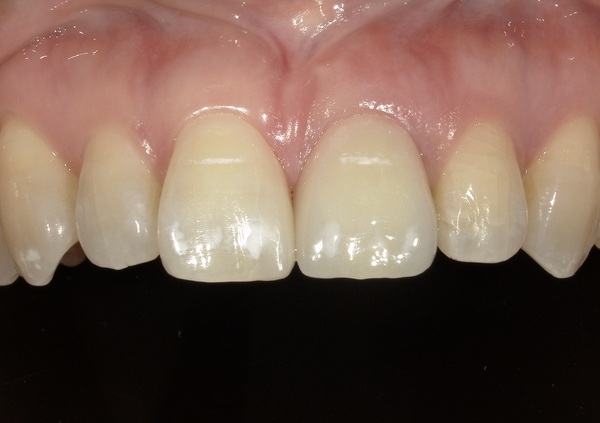

微調整を行い装着しました。こちらがセット後の写真になります。

患者様は、もともとのすきっ歯も改善され、自然な見た目となり、最初より綺麗になったと大変満足されております。また、治療期間は長くかかりましたが、両サイドの歯を削らずに審美的な治療ができたことにもとても喜ばれております。現在は年に2~3回メインテナンスで通院されております。

今回のケースでは歯間乳頭(歯と歯の間の三角形の歯茎)もしっかり維持されており、どの歯がインプラントにしたのかはほとんど分からないと思います。